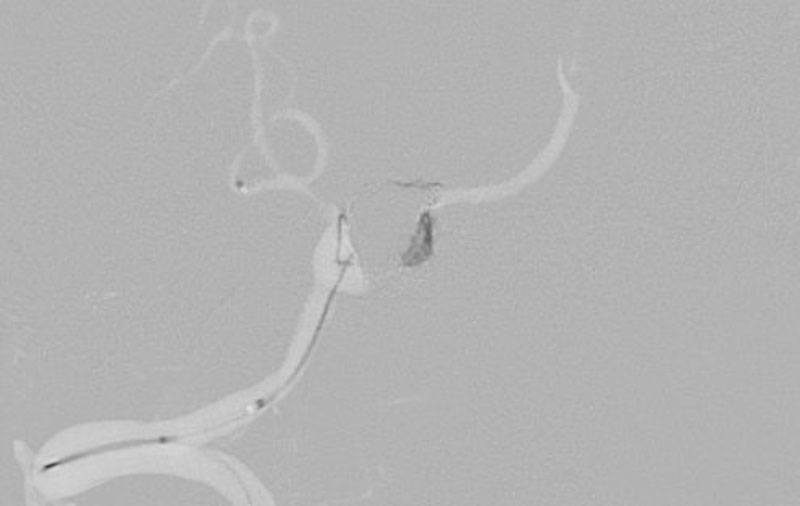

No.1203 手術後